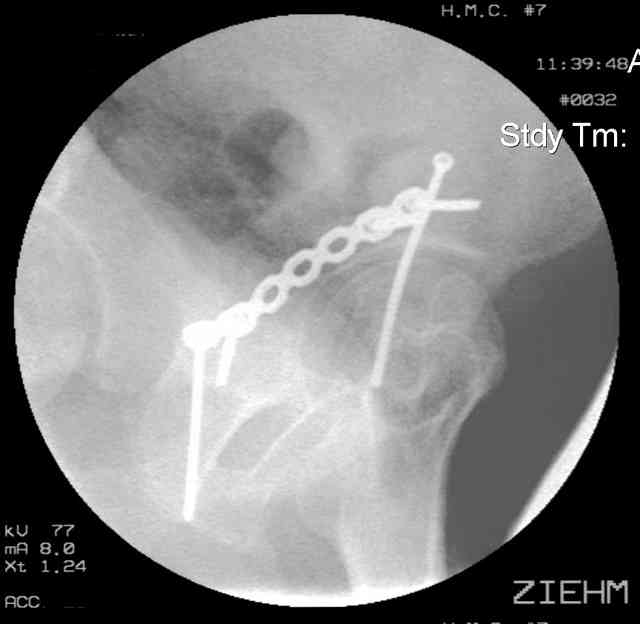

12.Prone Obturator-Outlet

Same with a contoured pelvic reconstruction plate applied and tensioned.

Prone Iliac Oblique

The other oblique reveals the extra-articular implants.... you know the AC screw is extra-articular from the other views.